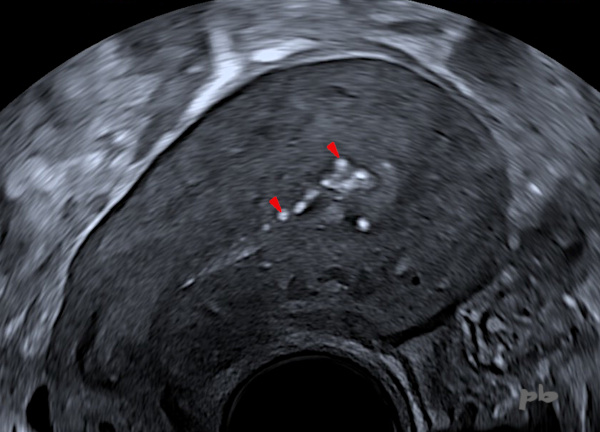

Révision utérine il y a 2 mois.

Echographie endovaginale.

Présence de calcifications (►) postérieures (le placenta était postérieur pendant la grossesse) : simples phénomènes cicatriciels en rapport avec le curetage, ou persistance de quelques résidus placentaires.